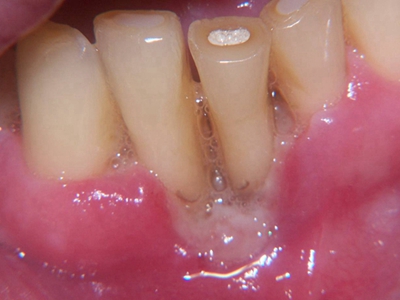

牙龈炎是发生于牙龈组织的炎症,患者可出现牙龈出血伴肿胀、发红、正常形态改变和偶尔不适等症状。本病主要由口腔卫生状况差导致,包括口腔不洁、牙菌斑等,诊断依据临床检查,治疗包括专业牙齿清洁和加强家庭口腔卫生。

牙龈炎可先引起牙齿与牙龈之间的沟(龈沟)加深,然后牙龈充血,炎症围绕一个或多个牙齿,伴牙龈乳头肿胀和易出血。一般无痛,可自行消退,也可维持轻度炎症数年。

牙龈炎常见的病因是口腔卫生差,不良的口腔卫生使牙菌斑沉积于牙齿与牙龈之间,造成龈沟加深,另外牙结石、不良修复体等也可造成牙龈炎的发生。